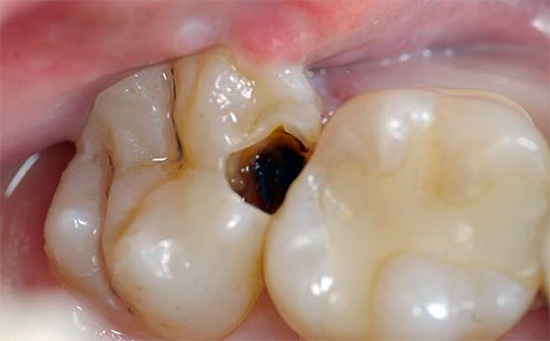

Mas na maioria das vezes os dentes doem devido a várias patologias: devido a cárie profunda, pulpite ou periodontite, e nesses casos a dor pode variar de leve e rápida a muito aguda e constante. Além disso, também pode ser observado inchaço das gengivas e bochechas (edema), febre, dor de cabeça e outros sintomas desagradáveis.

- Cárie, que em diferentes estágios pode se manifestar como dor fraca e que passa rapidamente, e dor bastante forte. Se você suprimir essa dor de dente em casa com pílulas, o processo de cárie inevitavelmente chegará à polpa, resultando em pulpite - e essa é uma dor muito mais intensa, e o tratamento desse dente estará associado à necessidade de remover o "nervo" dele. Geralmente, esse é um procedimento longo e caro, especialmente no caso de dentes multicanais.

- A pulpite, que se manifesta com dor de dente grave, geralmente piora à noite. Se, neste caso, você tentar ser tratado em casa, apenas aliviando a dor com a ajuda de comprimidos, poderá praticar periodontite, fluxo e fístulas purulentas nas gengivas. Além disso, em alguns casos, a extração dentária está longe de ser a conseqüência mais triste.